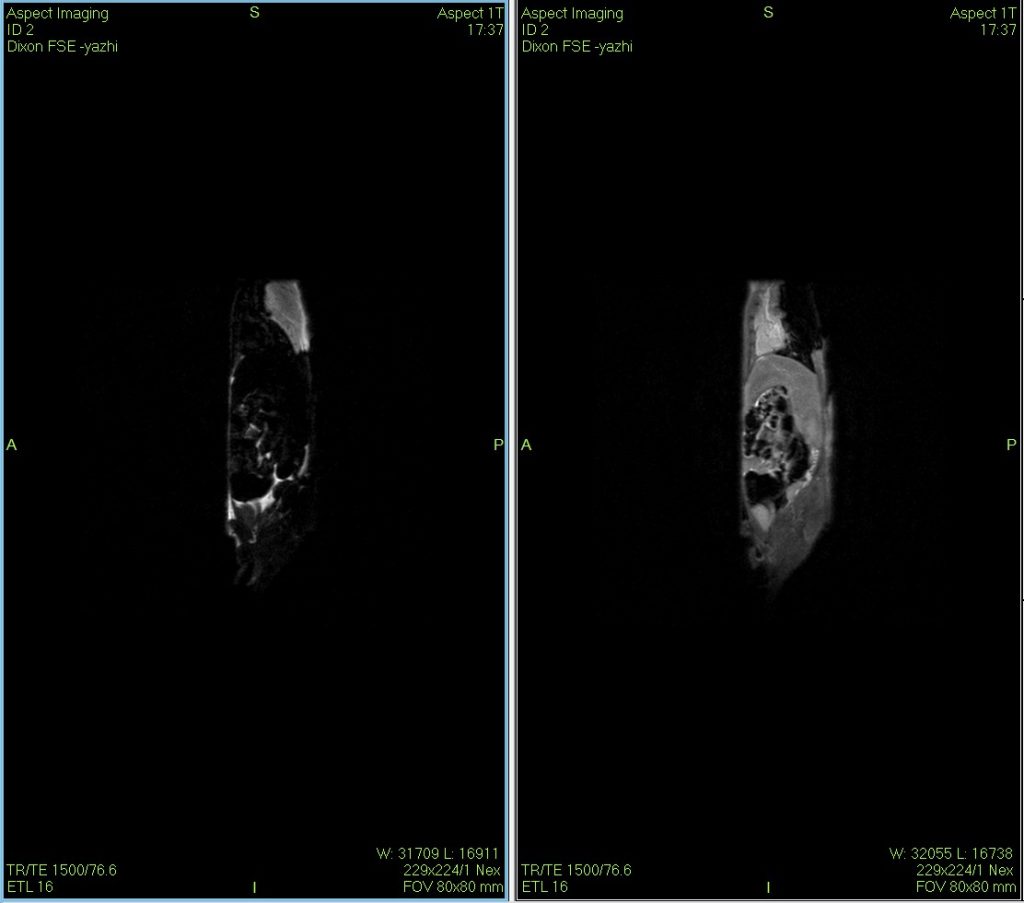

小鼠核磁共振Dixon水脂成像图

Dixon水脂分离技术是一种使用的核磁成像技术,在某些动物疾病模型的诊断、鉴别与治疗过程的评估上具有一定的独到之处。